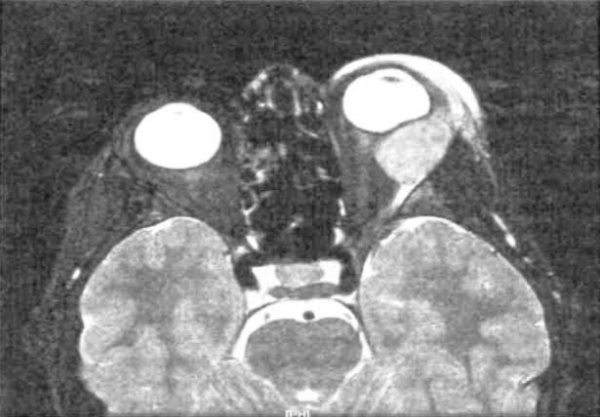

У 50-летнего мужчины, в течение 20 лет страдающего макроглобулинемией Вальденстрема, с верхневисочной стороны от левого глаза развилось безболезненное объемное образование, постепенно увеличивающееся в размерах. Аксиальная Т1 -взвешенная МРТ с гадолиниевым усилением: тот же пациент, что и на рисунке выше. Обратите внимание на контрастное объемное образование в области левой слезной железы. Корональная МРТ того же пациента: двусторонние образования в верхневисочных отделах глазниц. При исследовании биоптата диагностирована диффузная неходжкинская В-клеточная лимфома краевой зоны. После четырех недель терапии ритуксаном наблюдался выраженный эффект. Лимфоплазмоцитоидная опухоль. Блефароптоз и небольшой экзофтальм справа у мужчины 72 лет. КТ; аксиальная проекция: тот же пациент, что и на рисунке выше; в верхневисочной части глазницы определяется овоидная опухоль, поражающая в основном слезную железу. Опухоль иссечена через верхневисочную орбитотомию. Гистологический препарат новообразования, показанного на рисунке выше: определяются диффузные пласты мелких лимфоцитов и отдельные набухшие плазматические клетки (гематоксилин-эозин, х100).

Плазмоцитома глазницы как компонент миеломной болезни. У женщины 76 лет, в течение трех лет страдающей иммуноглобулин-С-лямбда множественной миеломой и получавшей химиотерапию, развился левосторонний экзофтальм. КТ, аксиальная проекция: та же пациентка, что и на рисунке выше; определяются диффузное объемное образование в височной части глазницы, смещение зрительного нерва в медиальную сторону, деструкция скуловой кости и прорастание опухоли в головной мозг и височную ямку. Микропрепарат новообразования, показанного на рисунке выше: отмечаются пласты атипичных плазматических клеток (гематоксилин-эозин, х75). Левосторонний экзофтальм и отек века у пациента 52 лет с диагностированной миеломной болезнью. Аксиальная Т1 -взвешенная МРТ с гадолиниевым усилением: тот же пациент, что и на рисунке выше. Видно крупное мягкотканное образование глазницы, поражающее слезную железу. Микропрепарат новообразования, показанного на рисунке выше: наблюдается злокачественная плазмоклеточная опухоль и митотическая активность (гематоксилин-эозин, х200).